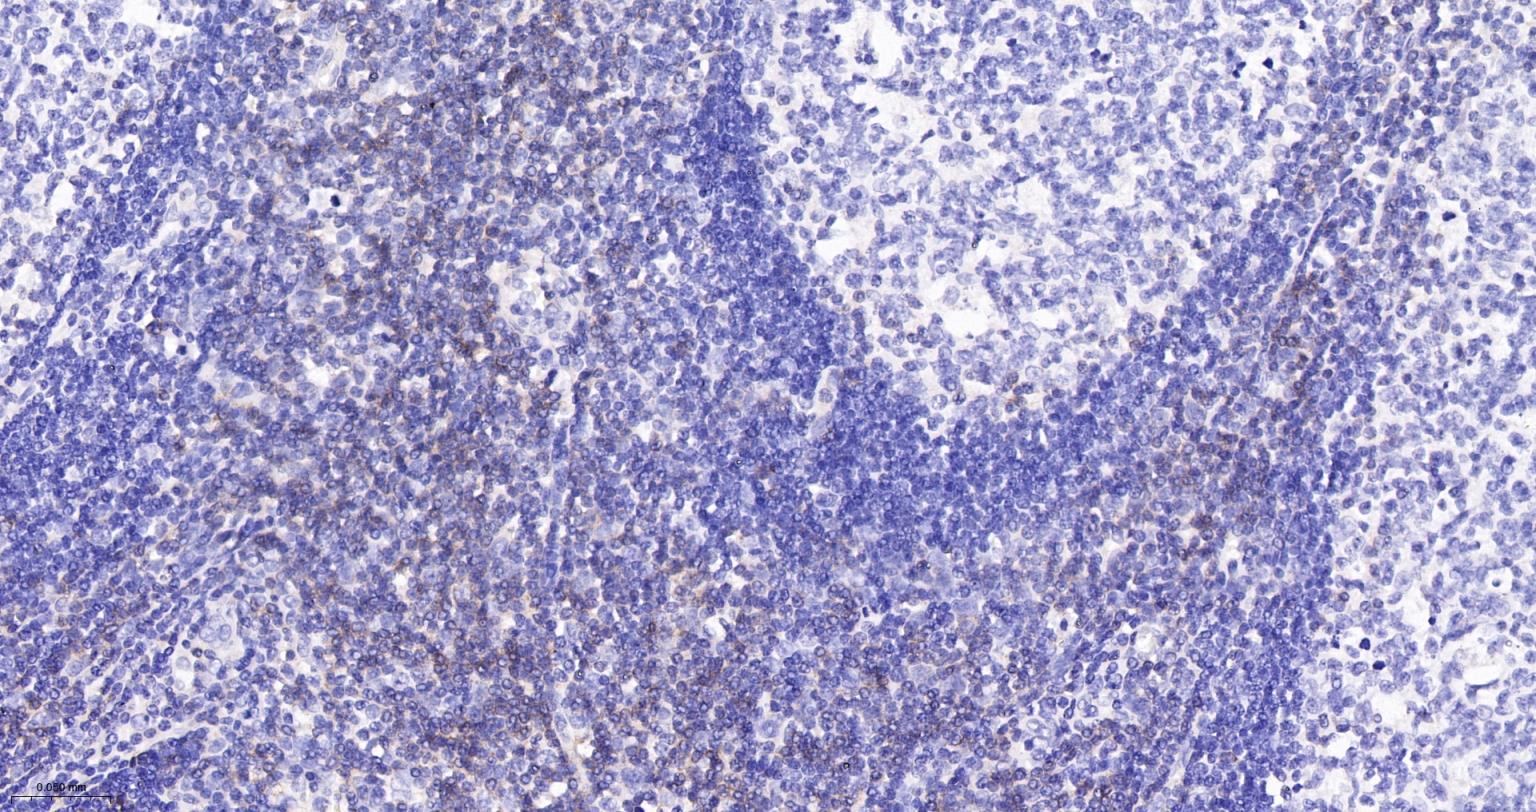

Tissue: Human tonsil Section type: Formalin fixed & Paraffin -embedded section Retrieval method: High temperature and high pressure Retrieval buffer: Tris/EDTA buffer, pH 9.0 Primary ab dilution: 1:1000 Primary ab incubation condition: 1 hour at room temperature Secondary ab: SP Kit(Rabbit) (sp-0023) Counter stain: Hematoxylin (Blue) Comment: Color brown is the positive signal for bsm-60390R